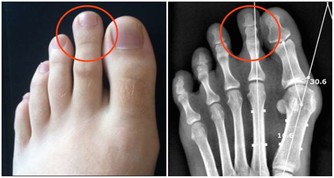

原來Josef是因為最近出現背痛、呼吸不順的症狀,才趕快赴往醫院檢查,起初他以為是肥胖因素導致身體出狀況,不過到院檢查後卻發現是肚子裡長著一顆腫瘤,大到已經擠壓到附近的器官:腎臟、肝臟與肺部,為求保命在醫生的建議下立即動手術移除腫瘤。

最後這場手術歷經六小時才成功切除腫瘤,待醫生一秤之下才知道這顆腫瘤重達27公斤。

術後的Josef仍須住院六個月積極治療,由於腫瘤與病人的腹部其他組織有相連,因此醫生也不敢大膽預測他的往後的病情會是如何,據了解,類似的大腫瘤病況在捷克境內相當罕見。